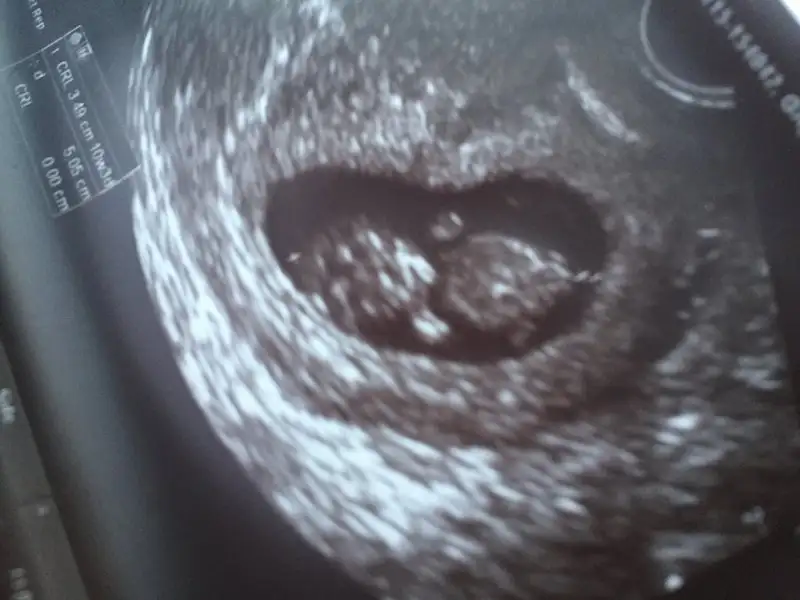

Evet ama senin doktorum ultrasonu baya ayrıntılı görünüyor.. ayakları bile belli.. ama 7,8,9 haftalık ultrason görüntüsünü at ona bakarlar